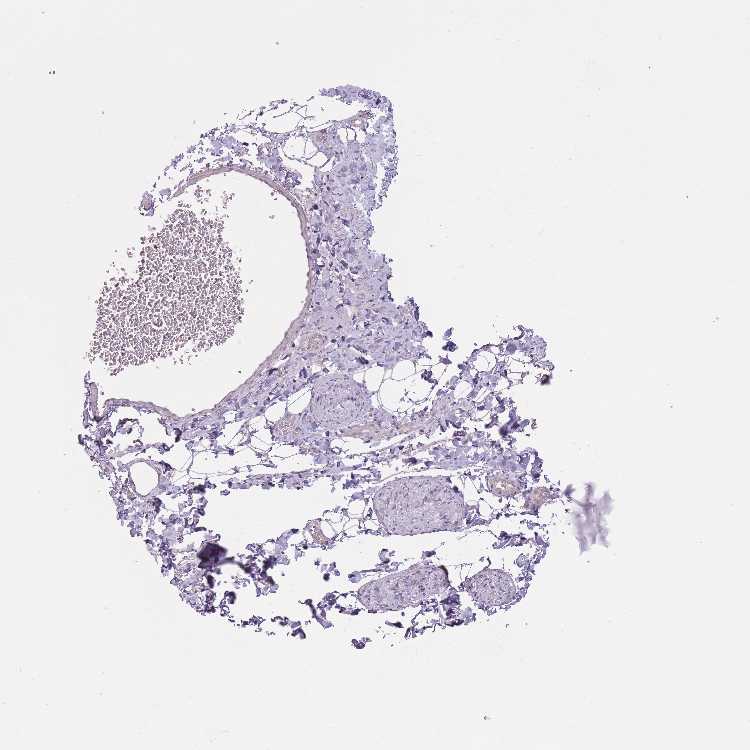

SOFT TISSUE 1 - Antibody stainingi

Antibody staining in the annotated cell types in the current human tissue is reported as not detected, low, medium, or high, based on conventional immunohistochemistry profiling in selected tissues. This score is based on the combination of the staining intensity and fraction of stained cells.

Each image is clickable and will lead to virtual microscopy that enables deeper exploration of all samples and also displays staining intensity scores, fraction scores and subcellular localization as well as patient and tissue information for each sample.

Antibody HPA041172Antibody HPA058652

Chondrocytes -Not detected

Fibroblasts Not detectedNot detected

Peripheral nerve Not detected-

SOFT TISSUE 2 - Antibody stainingi

Peripheral nerve Not detectedNot detected